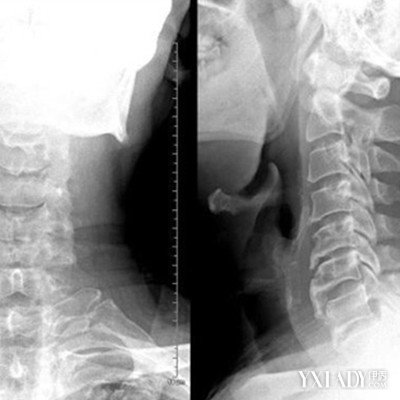

【图】正常颈椎图片展示 有7大保护颈椎小妙招